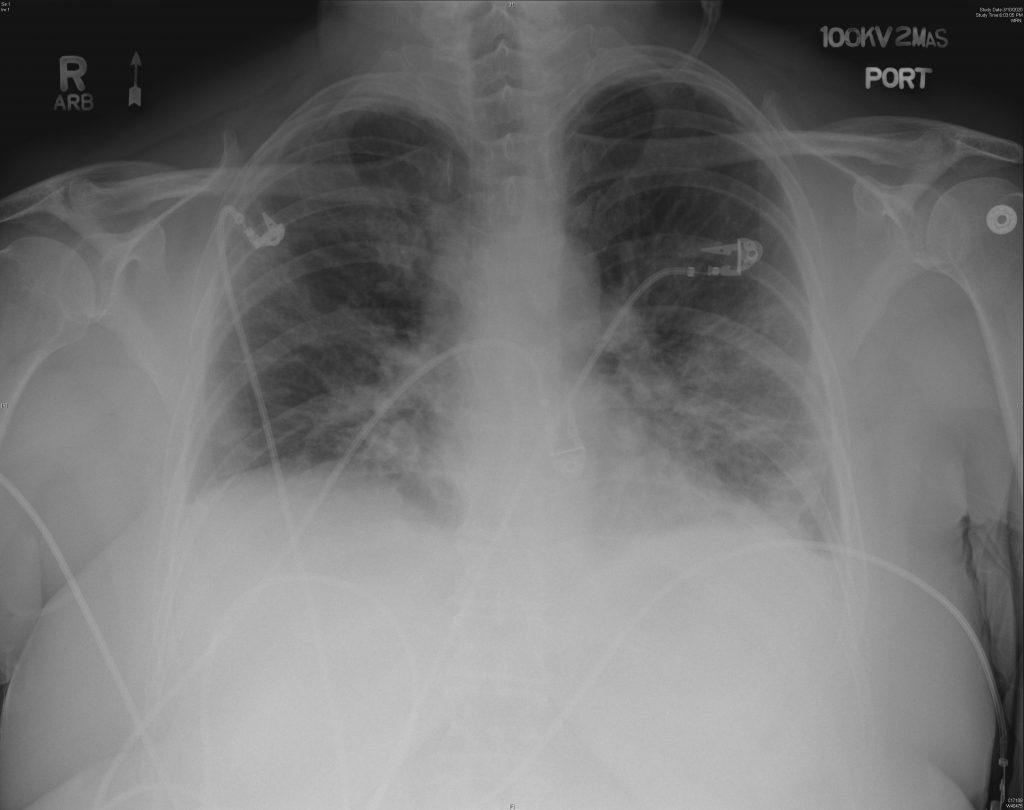

A new study published in the Canadian Medical Association Journal (CMAJ) examined ultrasound images taken from the lungs of a 64-year-old woman diagnosed with COVID-19, revealing how the virus can present itself in the lungs.

Credit: CMAJ. CMAJ

The ultrasound shows “pleural thickening, subpleural consolidation (also known as ‘skip lesion’) and multifocal B-lines,” researchers said.

The pleura are membranes that line the chest cavity and lungs, according to Mesothelioma.net, and they are typically thickened due to scarring, resulting in pleural thickening.

Consolidation occurs when your lungs are filled with something other than air, according to Healthline. It’s common with pneumonia and it often makes it difficult to breathe.

“These images show changes in the lung that occur due to the SARS-CoV-2 virus (which is responsible for COVID-19) infecting the lungs, and the body’s subsequent immune response to the infection,” said Dr. Anish Mitra, a critical care physician in Surrey, B.C.

“These ultrasound images indicate that there is inflammation in the lungs due to the infection.”

According to Mitra, ultrasound images such as these can help to guide treatment in patients with severe cases of COVID-19.

However, ultrasound should not be relied on during the diagnosis stage because inflammation — similar to what is shown in these images — can be seen in other viral pneumonias, including influenza.

“Rather, physicians can use lung ultrasound findings to help them make a diagnosis of COVID-19 or other diseases in the right clinical context,” Mitra said.